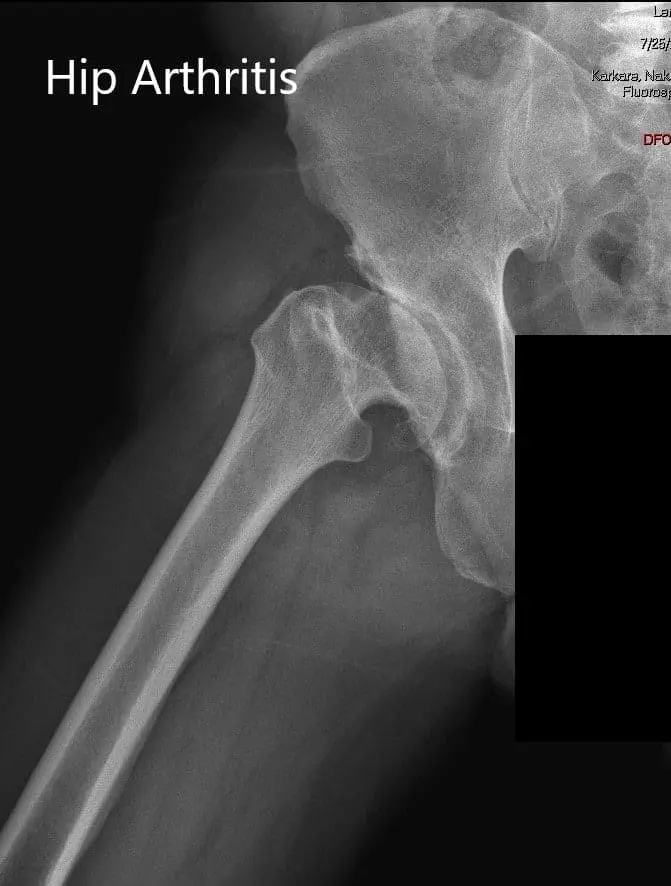

AP and lateral views of the right hip joint

AP and lateral views of the right hip joint - img 2

Imaging revealed markedly deformed right femoral head and impacted the femoral neck. There were severe degenerative changes of the right hip.